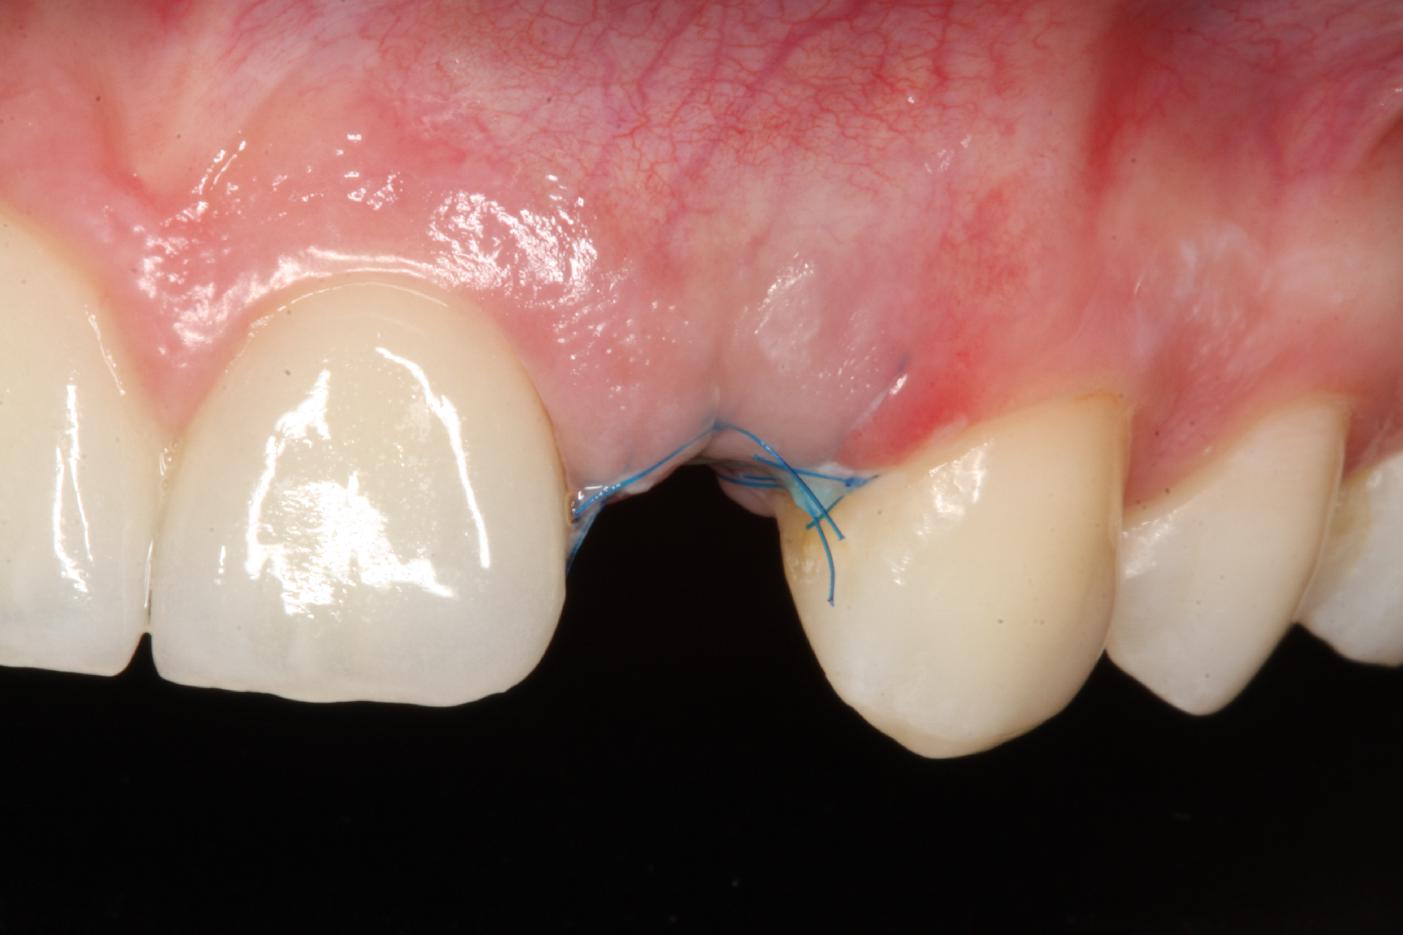

7/12 - Tension-free wound closure, occlusal viewSoft tissue thickening at immediate implant placement and GBR with mucoderm® and maxgraft® - Dr. A. Puisys

8/12 - Post-operative healing at 2 weeksSoft tissue thickening at immediate implant placement and GBR with mucoderm® and maxgraft® - Dr. A. Puisys